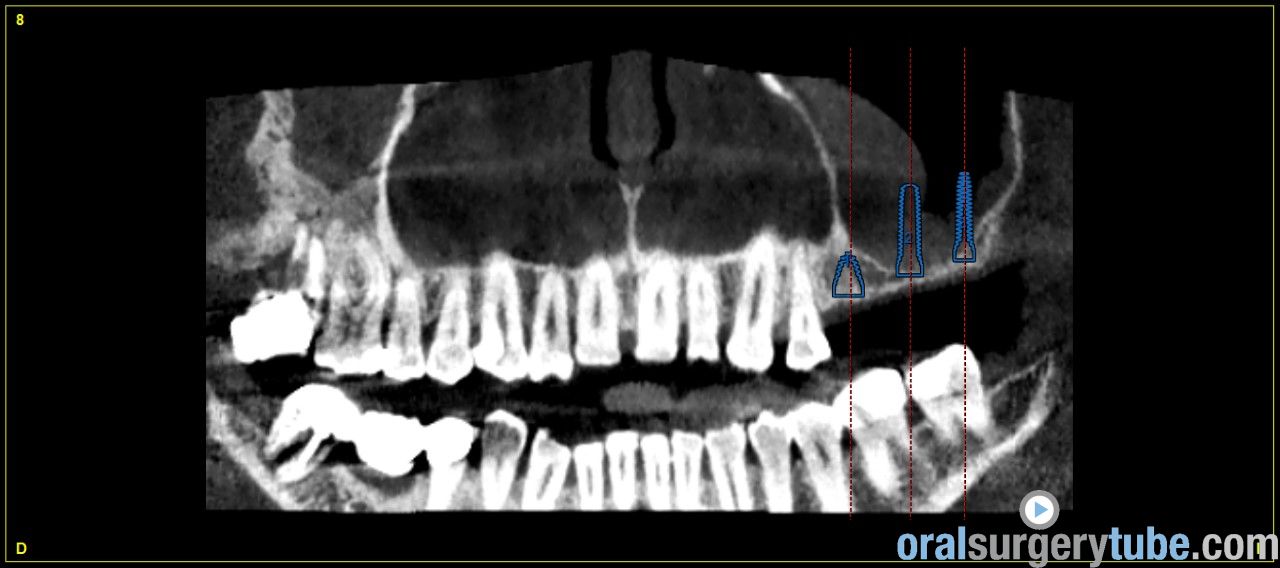

Engrosamiento mucoso

Estimados compañeros, me gustaria saber como abordaríais el seno izquierdo el cual como veis presenta engrosamiento mucoso. Haríais tratamiento previo? Gracias de antemano

Jesús me gustaría poder ver una vista panorámica, yo cada vez más tiro de pterigoideos, muchas veces elevando la mb de snneider y colocando el pterigoideo y la elevación sinusal.

Os envío imagenes. Se aprecia engrosamiento de la membrana del seno maxilar izdo.